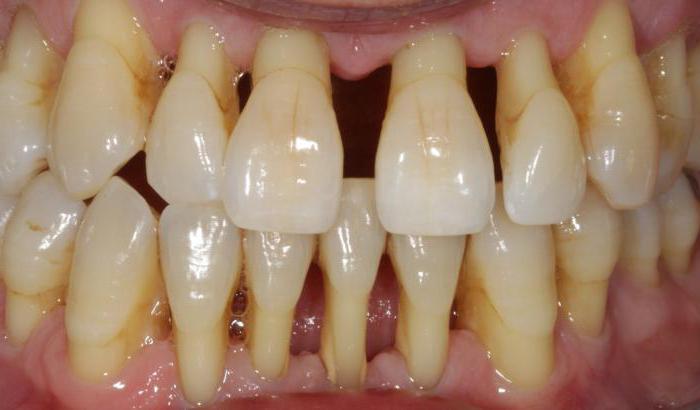

Parodontitis započinje upalom gingive, koja je crvena, bolna i krvari na dodir, a ukoliko se ne liječi, prelazi u parodontitis kad može doći i do ispadanja zuba. Parodontitis obuhvaća područja alveole, zubnog korijena i mekih tkiva koja ga okružuju.

Parodontologija – liječimo do nedavno neizlječivu bolest zuba

Parodontologija se veoma razvila – do nedavno se, u što računamo posljednjih 20-tak godina, parodontoza smatrala neizlječivom bolesti čime smo prihvaćali realnu činjenicu relativno brzog gubitka zubi i prijelaza na zubnu protezu. Novim metodama liječenja postigli smo izvrsne rezultate poput učvršćivanja zuba, ozdravljenja alveolarnog grebena i ozdravljenja zubnog mesa (gingive) uz adekvatnu higijenu i redovne posjete liječniku. Bez obzira o načinu tretmana (kirurški ili nekirurški) najbitniji čimbenik je vrijeme i rano javljanje pacijenta kako bi se odredila vrsta parodontne bolesti, napravio parodontološki status zuba i odredio tretman. Jedna od najbitnijih stvari kod održavanja paradontoze je higijena koja podrazumijeva ultrazvučno čišćenje kamenca, mekanu četkicu za higijenu i operativni zahvati za uklanjanje mikroorganizama i nekrotiziranog tkiva iz područja koje je zahvaćeno paradontozom. Ukoliko se odlučite na takav zahvat možemo Vam sa sigurnošću reći da će te zadržati vaše zube tamo gdje im je i mjesto, u čeljusti.